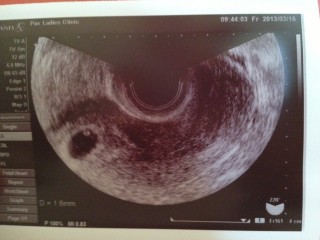

胎嚢、卵黄のうが確認されました。綺麗な丸でいいと言われました。大きさは1.22㎝です。みた瞬間ほっとしました。子宮外妊娠の説明はなかったですが少し心配だったし、つわりもないので心拍確認するまで油断は出来ないですが楽しみにしています\(^o^)/

まんまるくキレイに写ってくれました♪